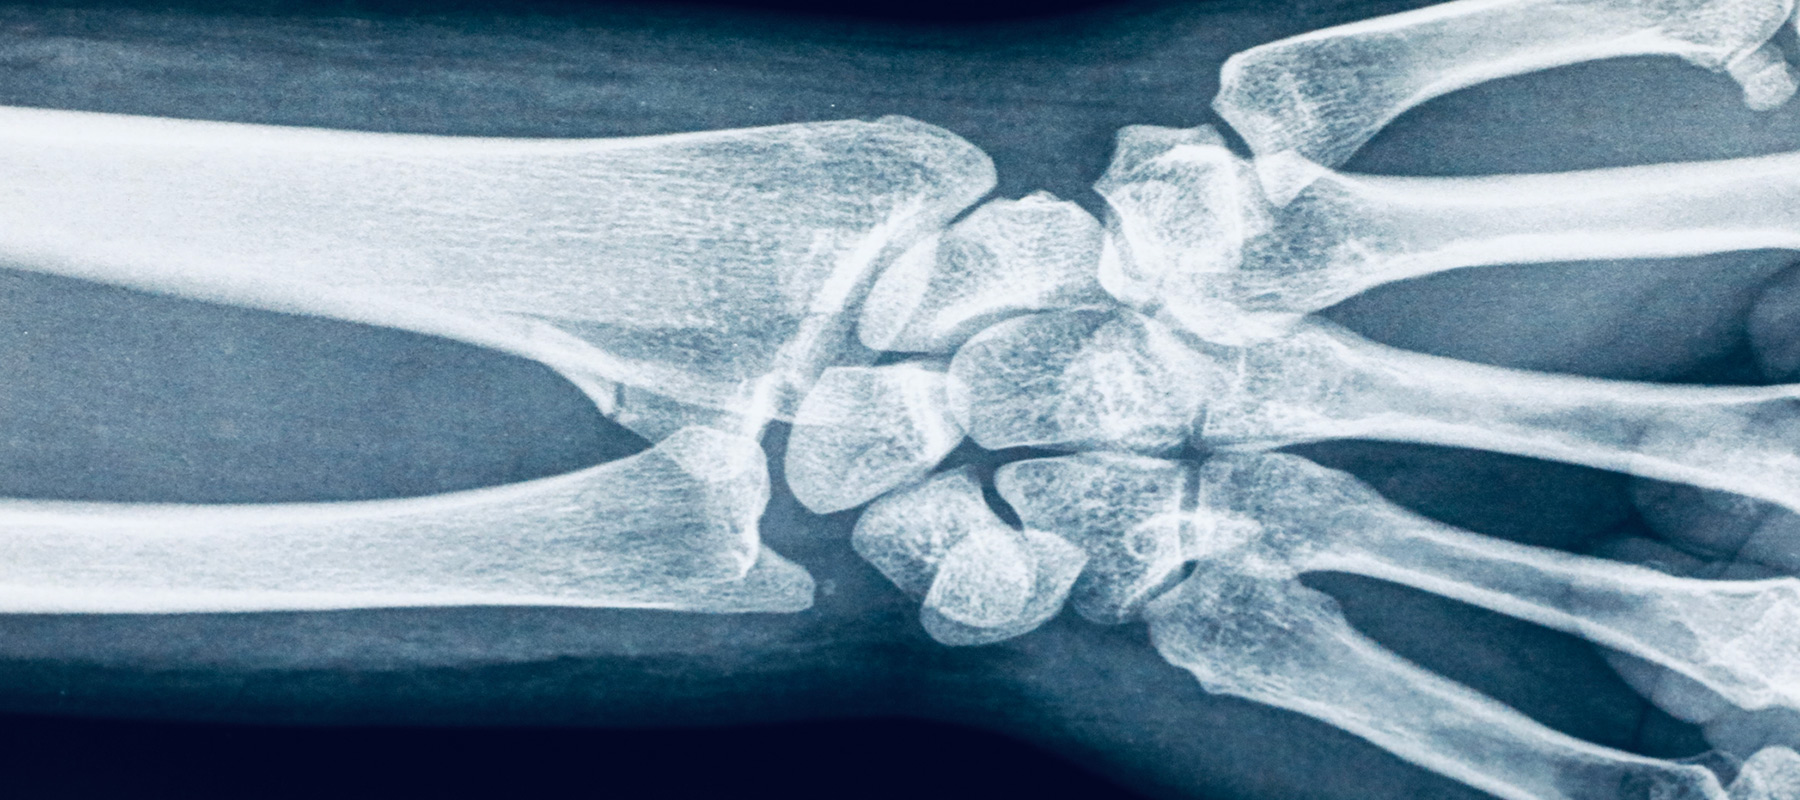

CBU's radiologic sciences degree provides students with comprehensive training in medical imaging techniques, including X-rays, MRI, and CT scans.

The College of Health Science offers an array of associate's, bachelor's and master's degrees tailored to prepare students for in-demand careers within healthcare. Our curriculum integrates essential concepts such as patient-centered care, evidence-based practice and interprofessional collaboration to foster well-rounded healthcare professionals. Students gain hands-on experience ensuring they are well-equipped to excel in fields such as athletic training, public health and radiology.